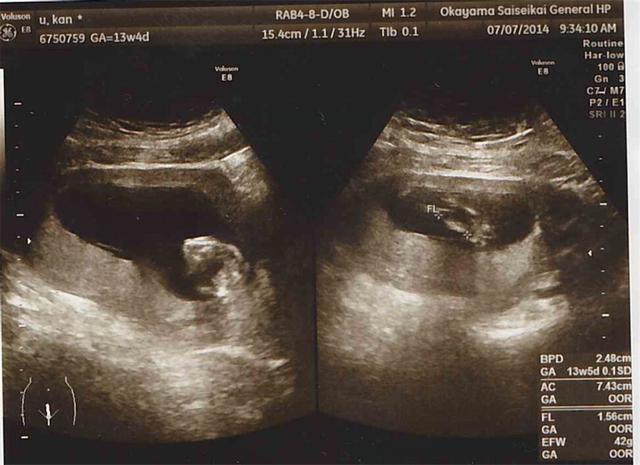

很多怀孕的妈妈对胎儿的性别非常好奇,现在生二胎的家庭越来越多,希望二胎也能如愿以偿。虽然现在的医院不能告诉准妈妈胎儿的性别,但还是难以满足妈妈们的好奇心。于是从检查中总想套出几句话,守口如瓶的B超室医生,他们会不会给准妈妈们一些暗示呢?

孕妈四、孕检发现自己怀的是双胞胎,但不知道是不是龙凤胎,在一次B超检查时,我问一样吗?医生说,不一样啊!后来生下宝宝后,果然是龙凤胎。